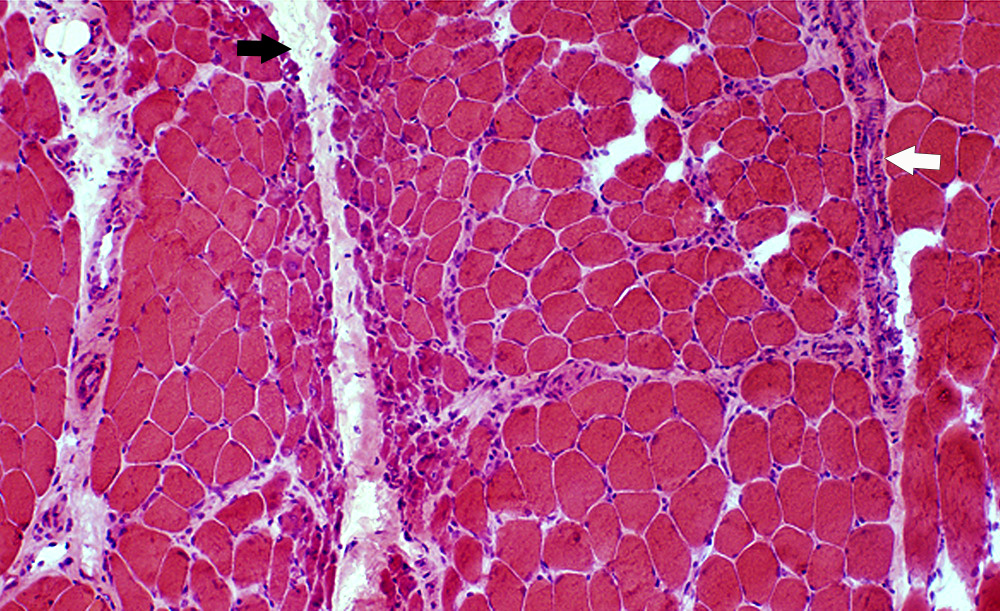

DM-VP: Perifascicular/Border-zone Muscle Fiber Smallness/Atrophy

Atrophic Muscle Fibers: Near Avascular Perimysial Connective tissue (Dark arrow) surrounding fascicle

Larger Muscle fibers: Within fascicle near intermediate sized perimysial vessels

Vessel in Vascular Perimysium: White Arrow

H&E stain

Perifascicular Muscle Fiber Atrophy: Along Avascular Perimysium

Atrophic perifascicular muscle fibers neighbor a long region of avascular perimysium with irregular structure (Center; Dark arrow).

Normal sized muscle fibers neighbor vascular perimysium (Sides; White arrow).